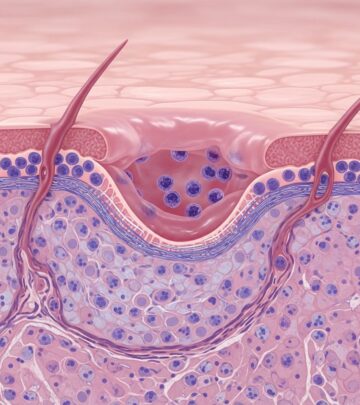

Radiographic Investigations In Melanoma: Essential Imaging Guide